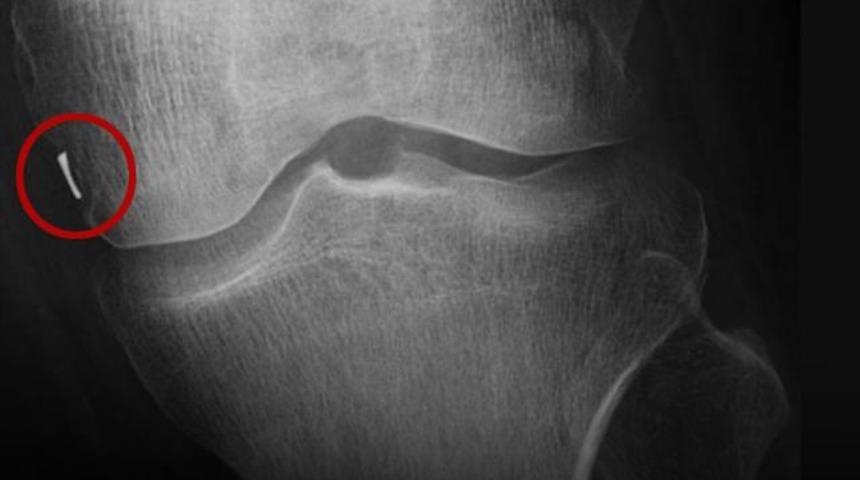

Geçen sürede ağrıları dinmeyen Özkan Durucan bu kez Batman’daki özel hastaneye başvurdu. Burada çekilen röntgende Durucan’ın dizinde yabancı metal cisim tespit edildi.

DİZİNDE TIBBİ KAMERA PARÇASI UNUTULMUŞ

Büyük şaşkınlık yaşayan Özkan Durucan, Diyarbakır’da ameliyat olduğu hastaneye gelerek doktorla görüşüp dizindeki cismin çıkarılmasını istedi. Ancak hastane ve doktor böyle bir ameliyatı gerçekleştirmeyeceklerini belirterek suçlamaları kabul etmedi. Bunun üzerine Adana’ya giden Özkan Durucan, özel hastanede ameliyata alındı. Operasyonla bacağındaki metal cisim çıkarıldı. Yapılan ilk incelemede cismin tıbbi kamera parçası olduğu belirlendi.